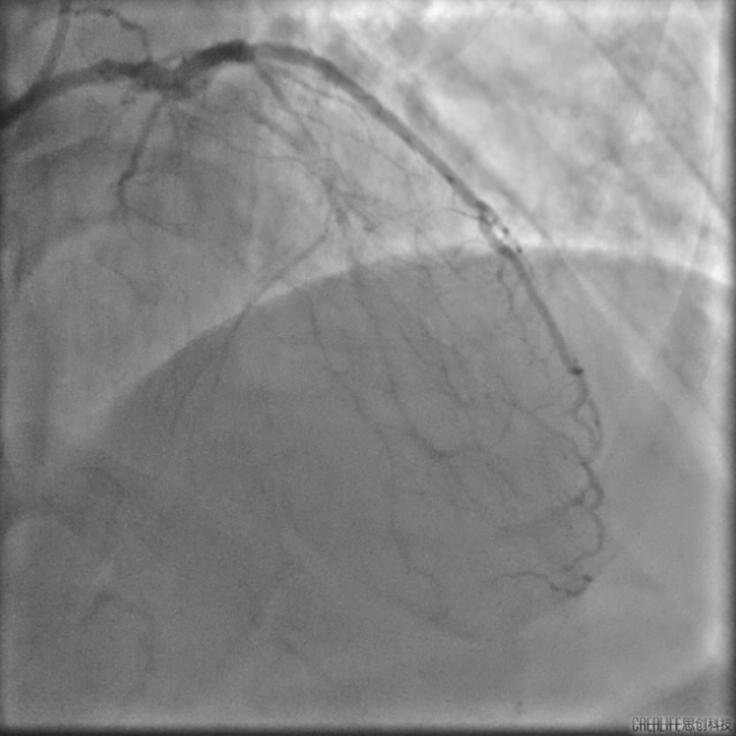

李怡教授使用该系统成功指导了一例前降支次全闭塞病例的PCI治疗。术中李怡教授通过IVUS细致地观察了患者前降支的近中段病变部位,在高清图像下对病变部位的管腔面积与斑块负荷等信息作出了详细的分析,并在成功为患者植入支架后,进一步对支架的植入效果进行了全面的评估及优化。李怡教授表示60MHzIVUS导管所生成的高清图像及管腔智能识别技术的辅助,给手术医生创造了更高效的读图分析环境,其功能的精准程度超出预期,令人印象深刻。

术前